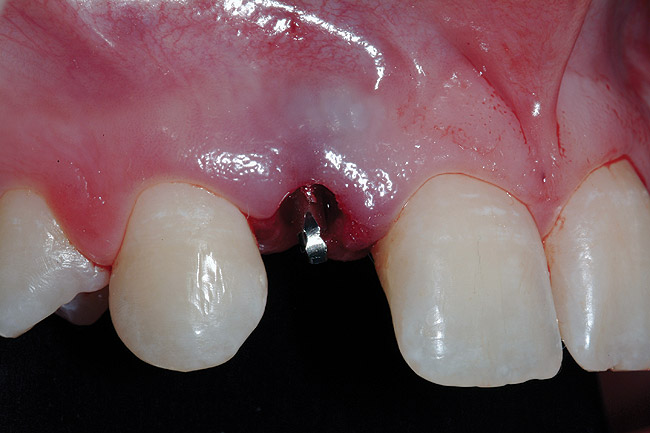

Figure 9  Minimally invasive small-diameter implant placement.

Figure 9

After atraumatic site preparation, two 3-mm diameter by 10-mm in length one-piece implants were seated at the No. 7 and No. 10 sites (Zimmer Dental, Carlsbad, CA) (Figure 9). Note the emergence profile formed by the esthetic recontouring of the crest of the ridge prior to implant site preparation. Confirmation of implant positioning was then verified by placing the TempStent II guide over the surgical sites (Figure 10). Ideally, because the heads of these implants are not wide and they do not lend themselves to gross preparation to reduce the facial aspect, the implants may not be suited for maxilla that has a steep angle. Minor preparation of the head can be performed facially but should be kept to a minimum.